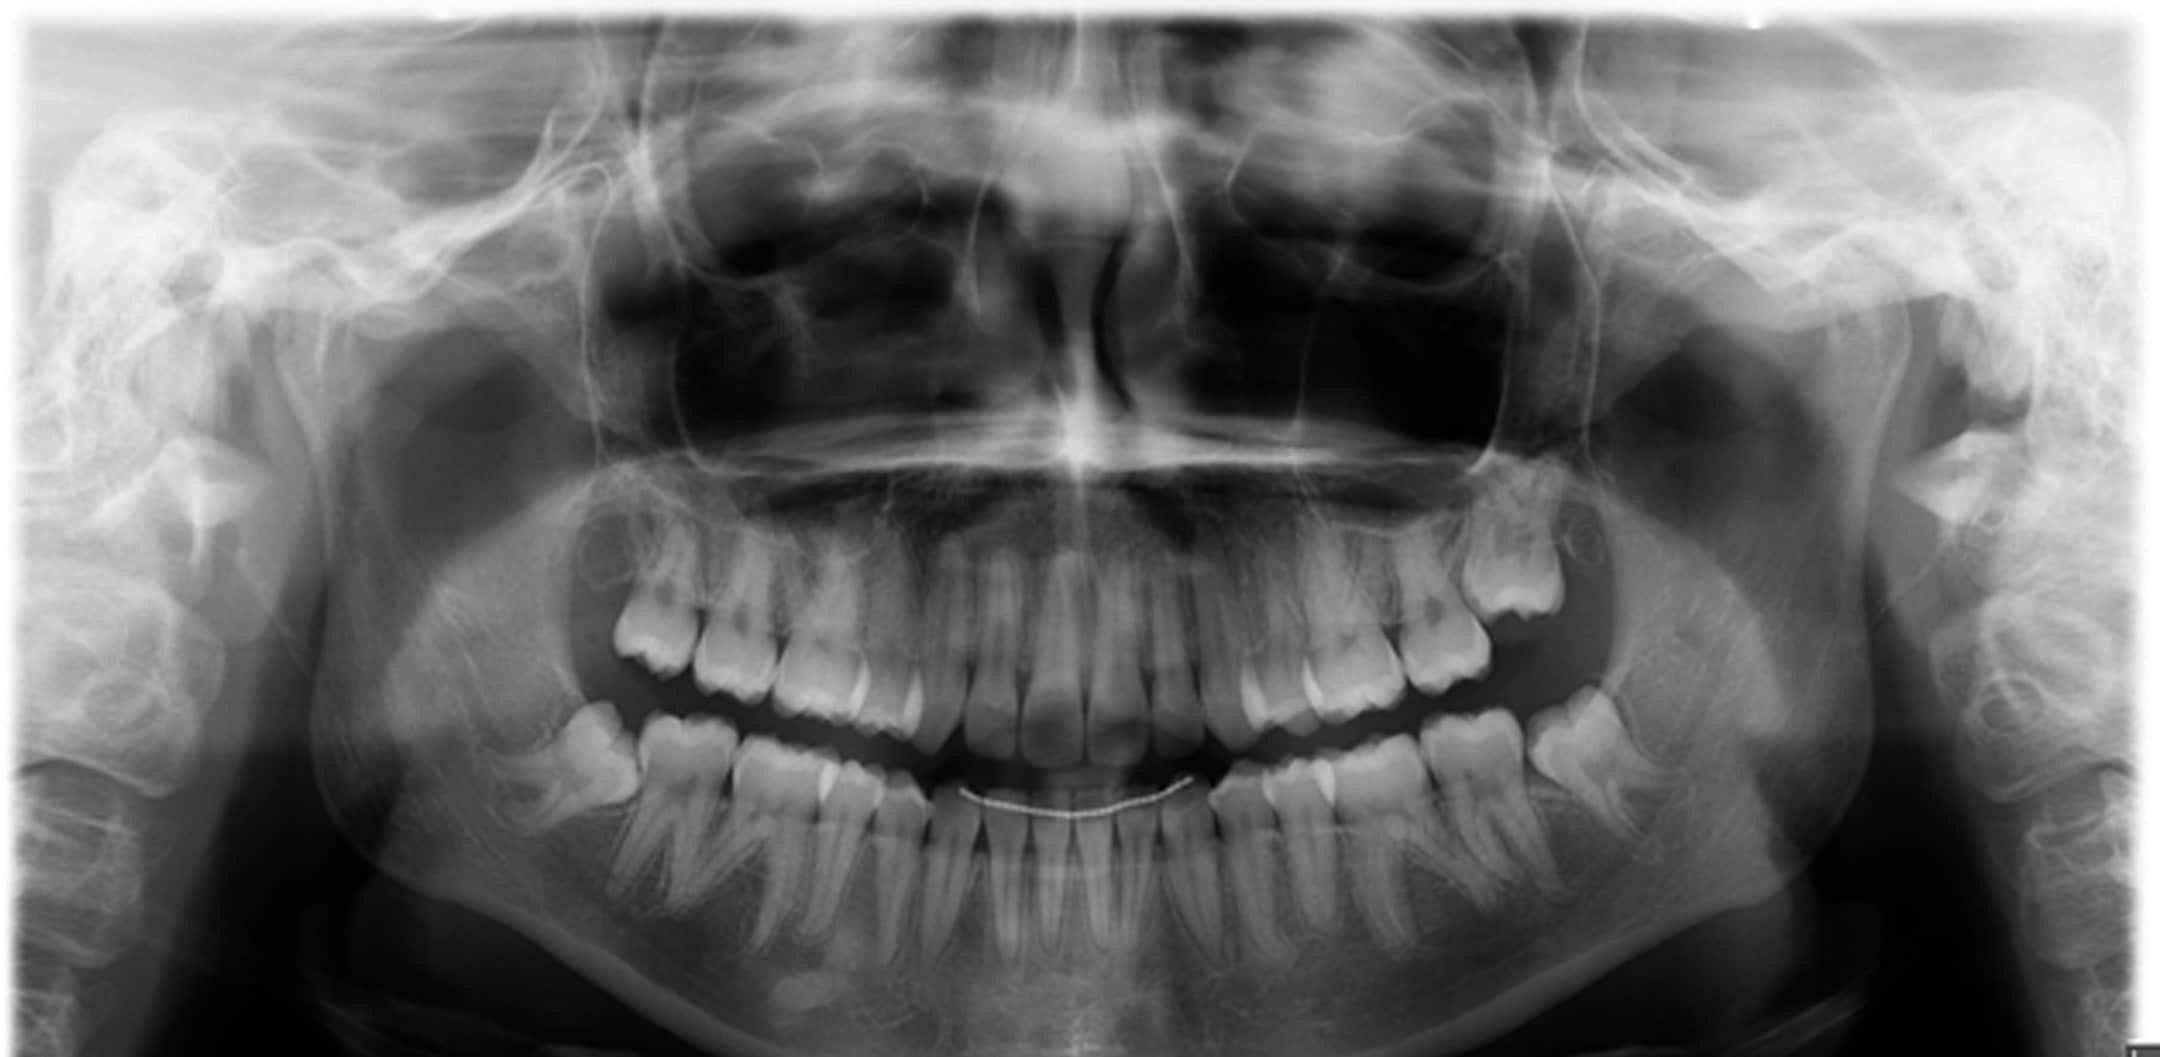

Comme pour chaque première visite, nous avons procédé à une analyse orthodontique complète : radiographies (téléradiographie latérale du crâne et orthopantomographie) mais aussi une série de photos des dents et du profil.

Les résultats de cette étude ont permis d’identifier plusieurs points-clés :

- Un manque de place marqué dans l’arcade supérieure.

- Des incisives supérieures qui penchaient franchement vers l’avant.

- Une mâchoire supérieure comprimée.

- Une ligne médiane supérieure décalée sur la gauche, ne coïncidant pas avec celle du bas.

Après analyse, le schéma le plus pertinent pour obtenir un sourire équilibré et une mastication optimale passait par l’extraction de deux prémolaires dans l’arcade supérieure. La ligne médiane étant décalée à gauche, il a fallu ajuster : extraction de la première prémolaire à droite et de la deuxième prémolaire à gauche. Ce choix permettait à la fois de réaligner la ligne médiane et d’assurer une occlusion correcte.